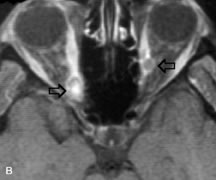

Inflammatory and Lymphoproliferative Lesions

Inflammatory conditions of the orbit, both idiopathic (inflammatory pseudotumor) and those of known causes, have been found to be hypointense to fat and isointense to muscle on Tl-weighted studies and isointense or slightly hyperintense to fat on T2-weighted images (Fig. 21).50,64,69 The more fibrous or sclerosing varieties have less signal intensity on T2-weighted images. Marked enhancement is seen in pseudotumor infiltrates after gadolinium administration.70 The same signal characteristics are demonstrated in patients with Tolosa-Hunt syndrome, with mass lesions seen in the cavernous sinuses and orbital apices.71

Fig. 21. A. T1-weighted MR scan demonstrates diffuse enlargement of both the superior rectus and levator palpebrae superioris muscles (single arrows). The involvement of the tendinous insertions and preseptal soft tissues (open arrows) as well as lack of involvement of other muscles helps differentiate this entity from thyroid-associated orbitopathy. B and C. Postcontrast fat-suppressed T1-weighted MR scans demonstrate extensive enhancement of the involved muscles as well as the preseptal (open arrows) and perinuscular tissues (double arrows).